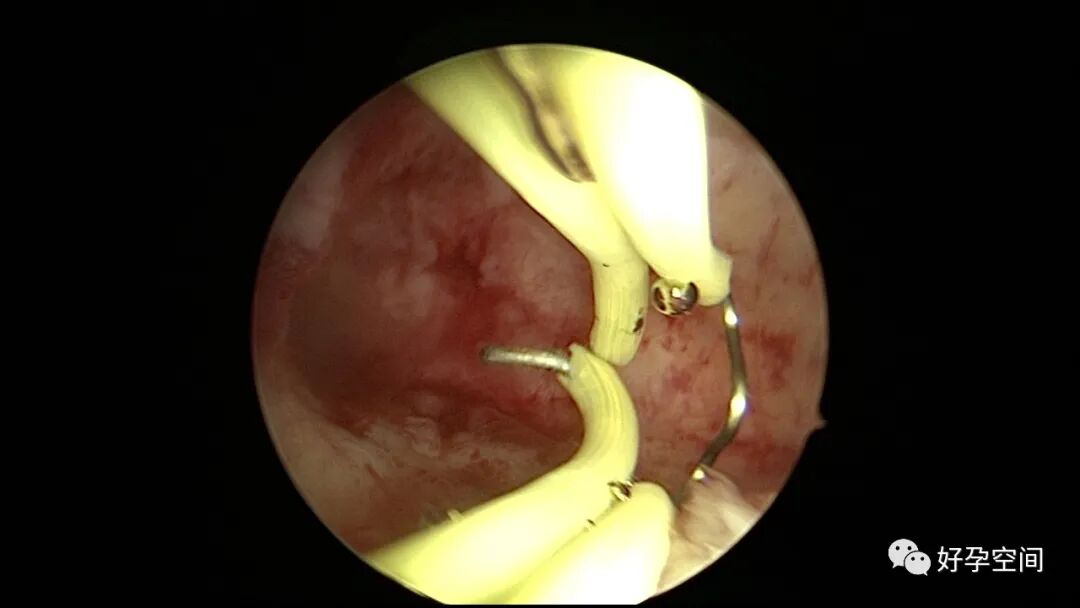

病例2:患者31岁,原发不孕,2019年11月在重庆某妇幼保健院做宫腹腔镜手术疏通输卵管,术中未取内膜活检,术后未孕。2021年7月在成都某大型生殖中心试管怀孕双胎(移植前未做宫腔镜检查及内膜活检),2021年11月孕4月双胎破水,在达州当地医院引产清宫,清宫术后40天复诊B超提示宫腔胚物残留。2022年1月到我院(眉山蕴缨妇产医院)行宫腔镜手术切除残留组织,2022年4月宫腔镜术后3个月复诊B超提示宫腔粘连,再次来我院行宫腔镜分粘。宫腔被覆一层沙丘状质脆增生组织,宫腔下段两侧壁内聚,行分粘术,取内膜送病检。

子宫内膜结核是由结核分枝杆菌在子宫内膜部位种植引起的炎症,是仅次于输卵管结核的常见女性生殖器结核。子宫内膜结核常由输卵管结核蔓延而来,多继发于盆腔腹膜结核或肺结核。子宫内膜结核的超声表现主要为:子宫内膜回声不均匀、宫腔内结节样病灶、宫腔内强回声灶、单纯的子宫内膜薄等。盆腹腔超声显示输卵管炎性表现:输卵管增粗、肥厚、扭曲、僵硬、输卵管积液积脓、卵巢旁混合性包块、输卵管系膜囊肿、盆腔包裹性积液等。术中所见:盆腹腔组织粘连、盆腹腔粟粒样结节、结核球、脓肿等,输卵管伞端烟斗样外翻,输卵管内充满淡黄色干酪样或豆渣样组织。宫腔镜显示宫腔狭窄、宫壁僵硬、宫内膜肉芽肿样增生、内膜质脆易刮除、干酪样组织、脓液等。

温宝宁等将子宫内膜结核宫腔镜检查的镜下表现分为:①宫腔形态、大小正常,双侧输卵管开口可见,子宫内膜发红、增厚,局部突起,表面可见少量质脆的小颗粒状赘生物,可刮出质脆的子宫内膜组织;②宫腔形态正常,但是宫腔内无正常子宫内膜,均被覆一层苍白的绒毛状或棉絮状质脆组织,血管少,无异形血管,宫腔内病灶与正常组织分界明显;③宫腔形态异常,呈窄桶状,子宫内膜瘢痕化,输卵管开口细小,甚至宫角消失。